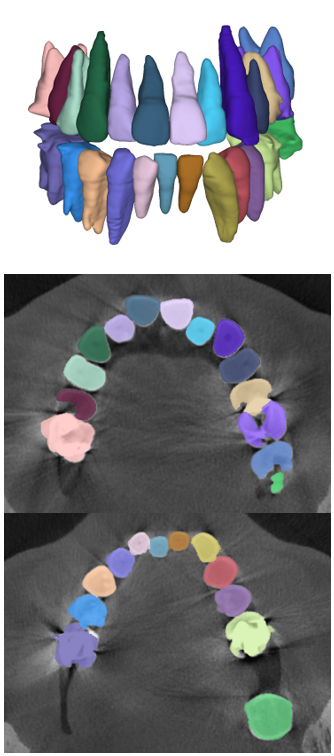

The manual seeded level-set methods [6, 7] demonstrate inferior performances while segmenting teeth with predominant metal artifacts (Table II). The energy-based (i.e., level-set function) algorithmic approach failed while defining an optimum stopping criterion (Fig. 12b). The AJI measures for level-set methods are omitted because the box detectors do not exist in the level-set-based methods. In particular, the low precision and sensitivity values indicate that level-set methods have over-segmented or under-segmented the teeth in many cases (Figs. 12b and 13a). The accuracies of the Mask-RCNN [17] and ToothNet [11] showed comparable performance to the level-set-based methods. The instance segmentation framework successfully detected and segmented the teeth automatically. However, it failed to detect all the teeth regions accurately, which resulted in a degradation of the segmentation performance. Moreover, the performance of the segmentation itself also showed low accuracy owing to the metal artifacts (Figs. 12c and 12d). Figure 13 illustrates the more severe conditions of metal artifacts. The performance of the detection and segmentation processes significantly degraded in ToothNet [11] (Fig. 13b) and Mask-RCNN [17] (Fig. 13c). Conversely, our proposed method outperformed the other state-of-the-art methods (Figs. 12e and 13d); further, the comparison between the PA- and non-PA-based results also demonstrated that the employment of a PA detector significantly improved the proposed architecture (Table II). The superior AJI value clearly shows that successful detection improved the overall performance.